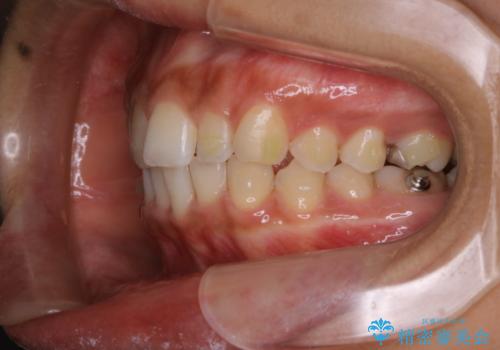

- インビザラインでの矯正治療中に、着色や汚れが気になるとのことでした。PMTC60分コースを行いました。

インビザライン治療中には、歯の表面にアタッチメント(効率的に歯の移動をするもの)を設定します。そのため歯ブラシでは届きにくい細かい部分などに、歯石や着色がついてしまうことがあります。着色などを放置していると、着色なのか、虫歯なのかの判別もしずらく正確にお口の中の状態を診断できません。